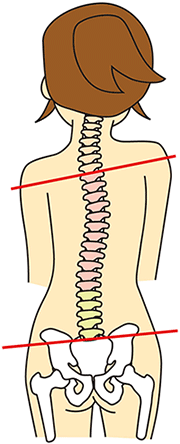

ズバリ「身体のゆがみ」です。

身体の歪みが臀部・下肢周辺に負担をかけて痛みとなっています。

つまり、歪むことで「動きが良い箇所」と「動きが悪い箇所」が出ています。